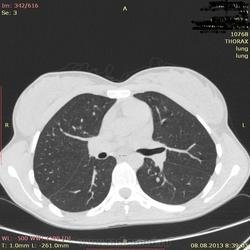

Здраствуйте, коллеги. Нужна ваша помощь молодая девушка 21 г. в течении 2-х лет беспокоит субфибрильная температура, период.гол. боль. В прошлом году сделала ОГК зак: туберкулема. Ей сказали что она перенесла тбс. на ногах, лечение не принимала. Сдавала все анализы без изменении.Родная сестра 3 года назад перенесла тбс.

Туберкулёма в 6-ке.

Распада не вижу, очагов отсева тоже. Контроль и к фтизиатру.

По показанным изображениям данных за активность нет, но без дайкома однозначно не сказать. Посмотрите в MIP при толщине среза 4-6 мм очаги. Если у девушки иммунодефицит любого генеза, то картина даже через несколько дней может кардинально поменяться, так что в любом случае конс.фтизиатра.

Справа в С6 - неправильной округлой формы образование повышенной интенсивности с включениями извести. Данное образование связано с корнем лёгкого бронхо-сосудистой "дорожкой". Рекомендовано анализ мокроты на МБТ!